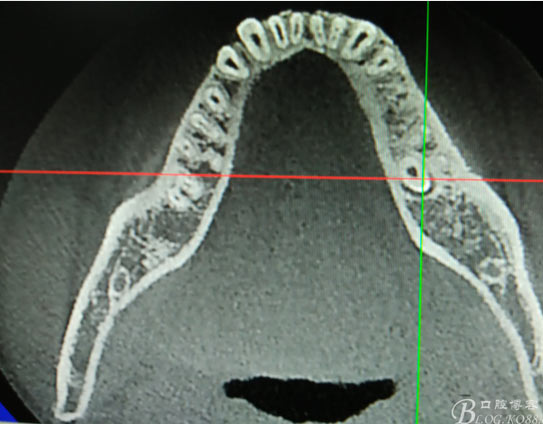

患者、盧xx、男、19歲。主訴:左側(cè)下頜乳磨牙未脫落,要求檢查。專科檢查:左側(cè)下頜第二乳磨牙有充填物。無松動,全景片檢查。35移位至36、37之間。頰舌側(cè)均不能觸及隆起。CBCT檢查:35位于36、37的舌側(cè)。表面骨質(zhì)約2mm左右。35完全骨埋伏,36的遠中牙根疑是吸收。建議35暫觀察。置留不取。患者要求拔除擔心壓迫36牙根或者發(fā)生囊性變。術(shù)前簽手術(shù)同意書。

圖1.術(shù)前的全景片影像檢查,35移位至36、37之間。